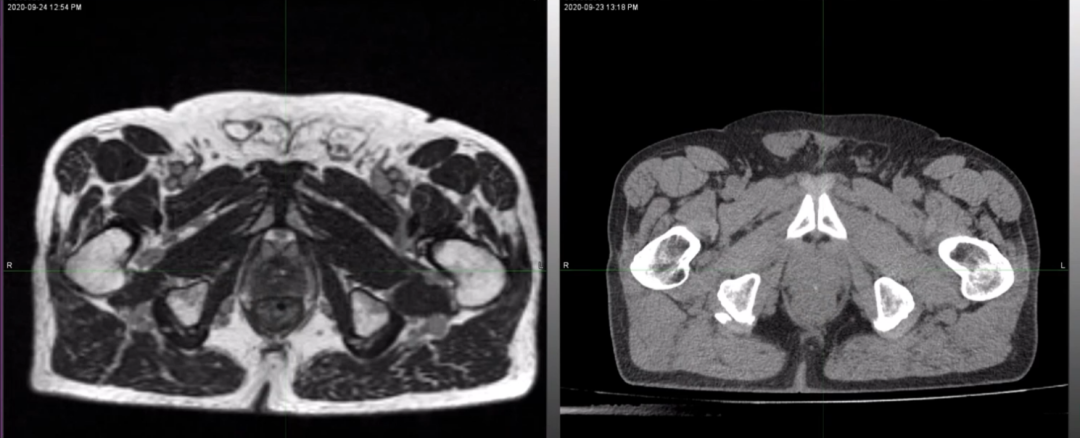

另外,Dr. Camilleri还展示了一位髋关节置换术后前列腺患者MRIdian 0.35T MRI影像和CT定位图像,MRIdian MRI图像受金属髋关节假体影响较小,仍能看清靶区和所有危及器官,见Figure 5。所以,仍然能为患者提供每日在线自适应放疗计划,但值得注意的是,射束必须避开金属髋关节,见Figure 6。

Figure 5 Dr. Camilleri展示的髋关节置换术后前列腺患者MRIdian 0.35T MRI影像(左)和CT定位图像(右),MRIdian MRI图像受金属髋关节假体影响较小